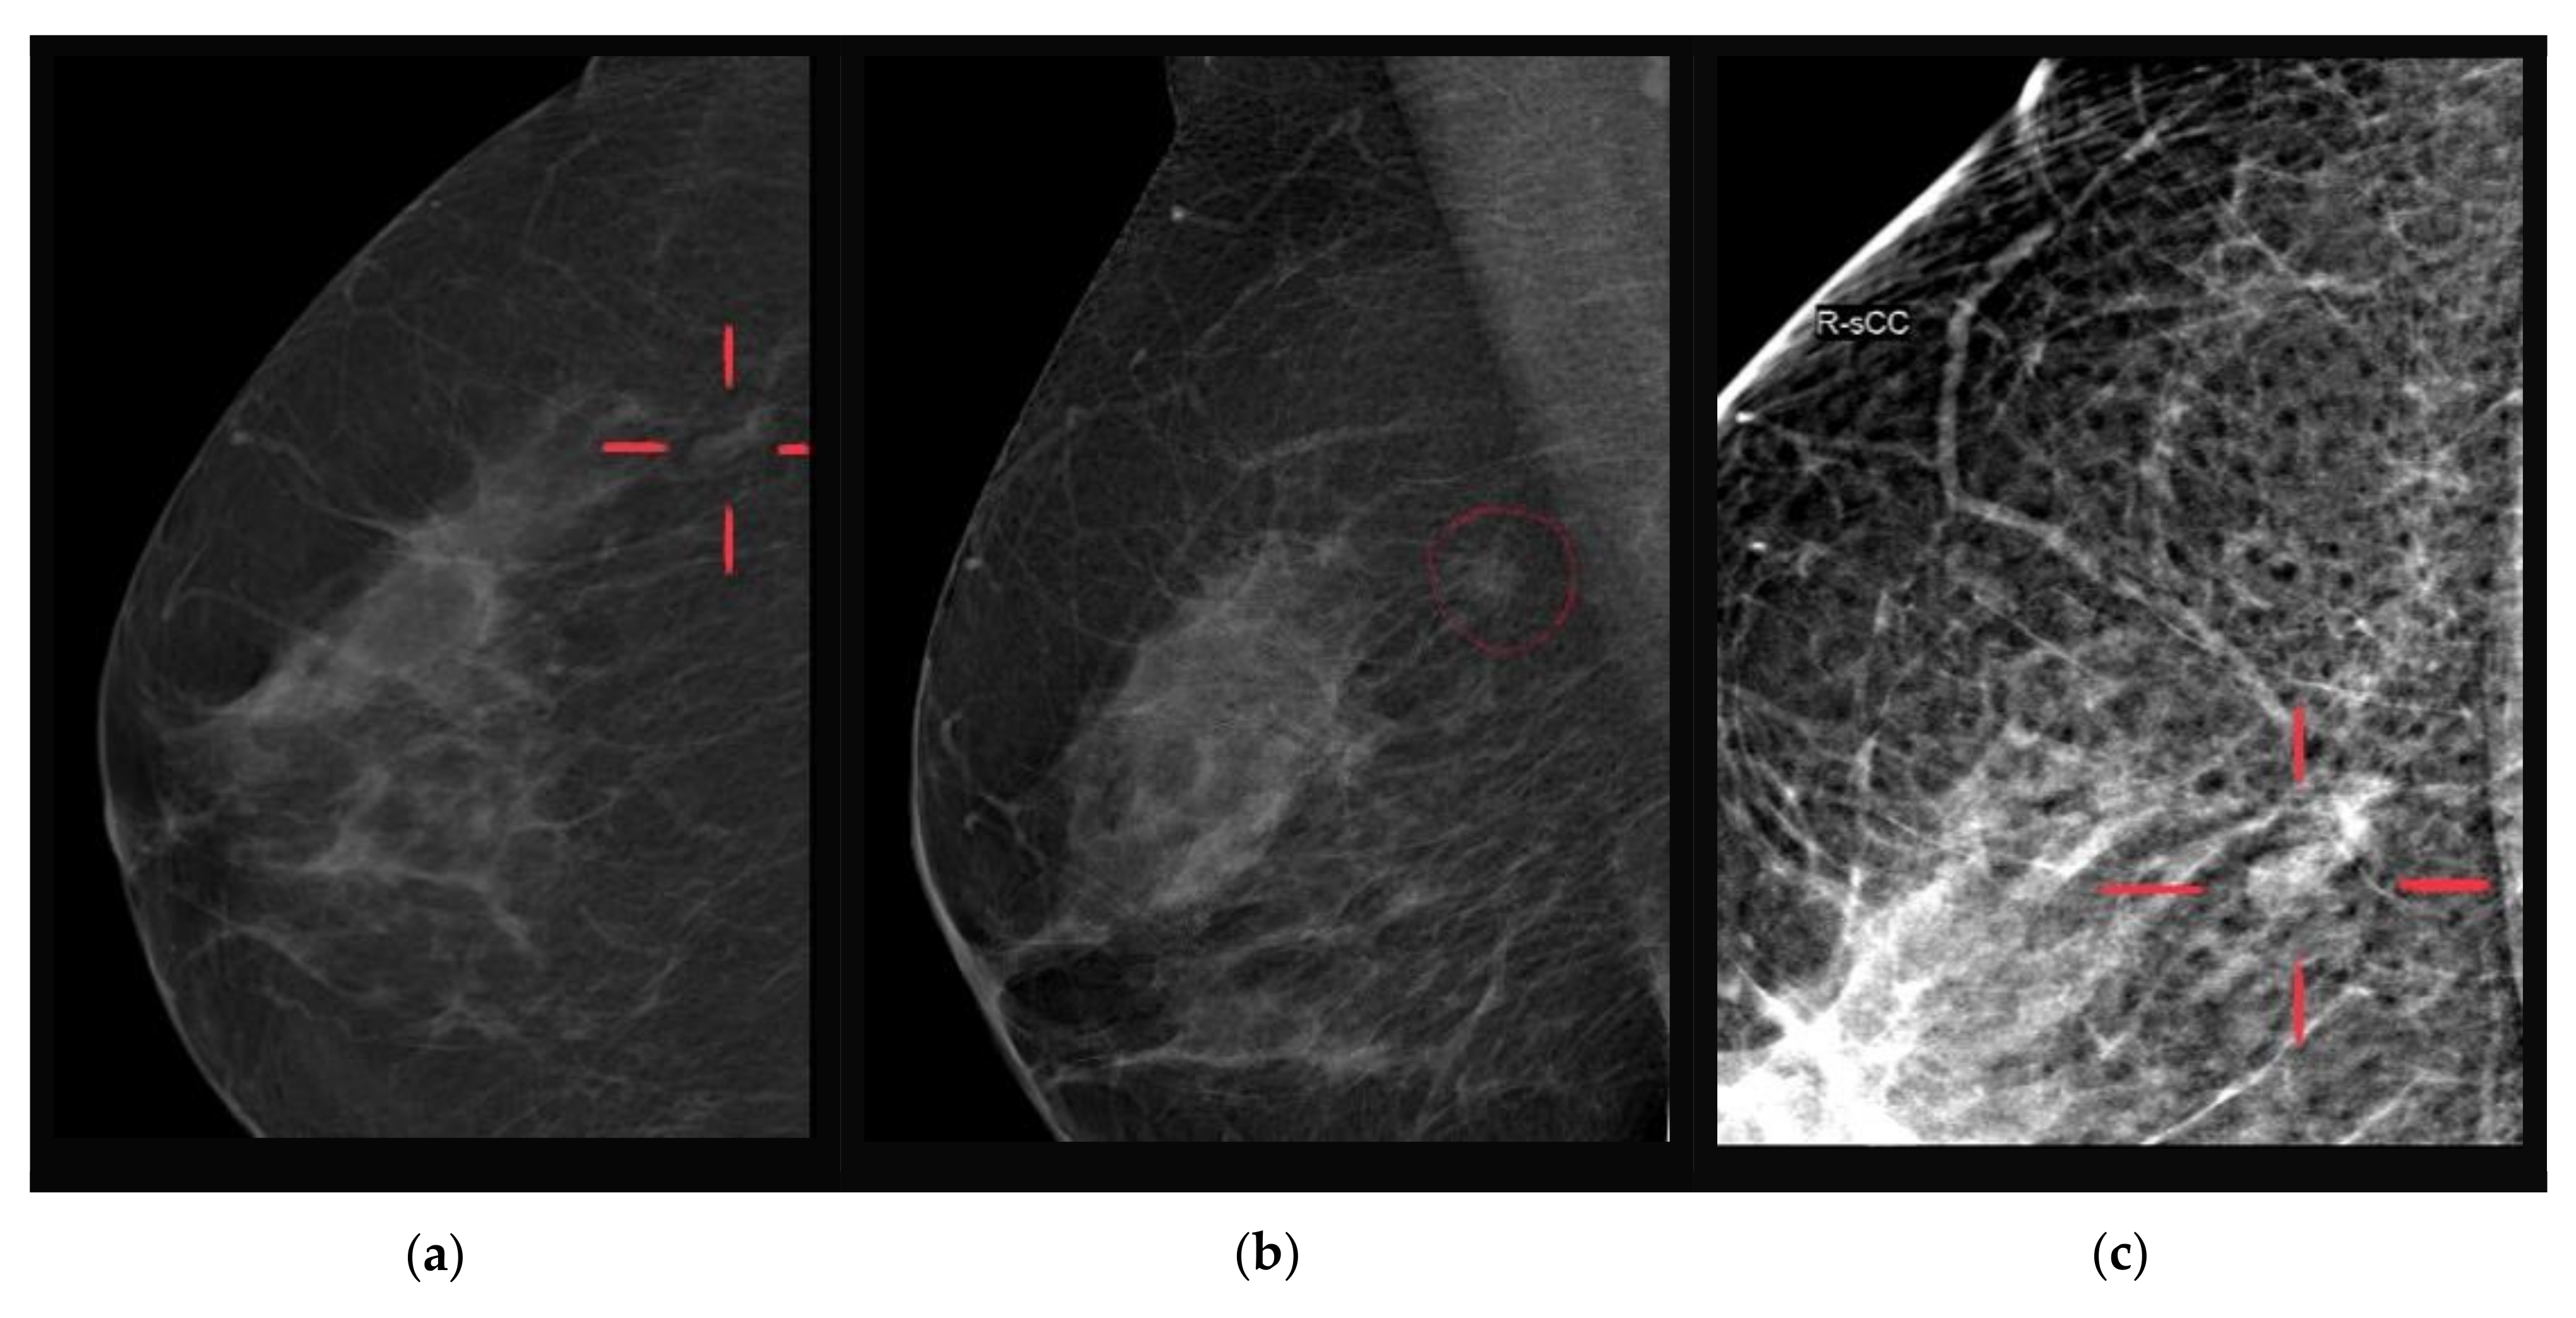

6. Imaging Findings